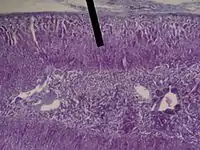

The zona fasciculata (sometimes, fascicular or fasciculate zone) constitutes the middle and also the widest zone of the adrenal cortex, sitting directly beneath the zona glomerulosa. Constituent cells are organized into bundles or "fascicles".

adrenal gland (zona fasciculata layer).